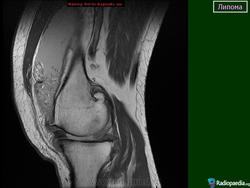

Случай 16: липома колена - ультразвук

Случай 23: липома бедра